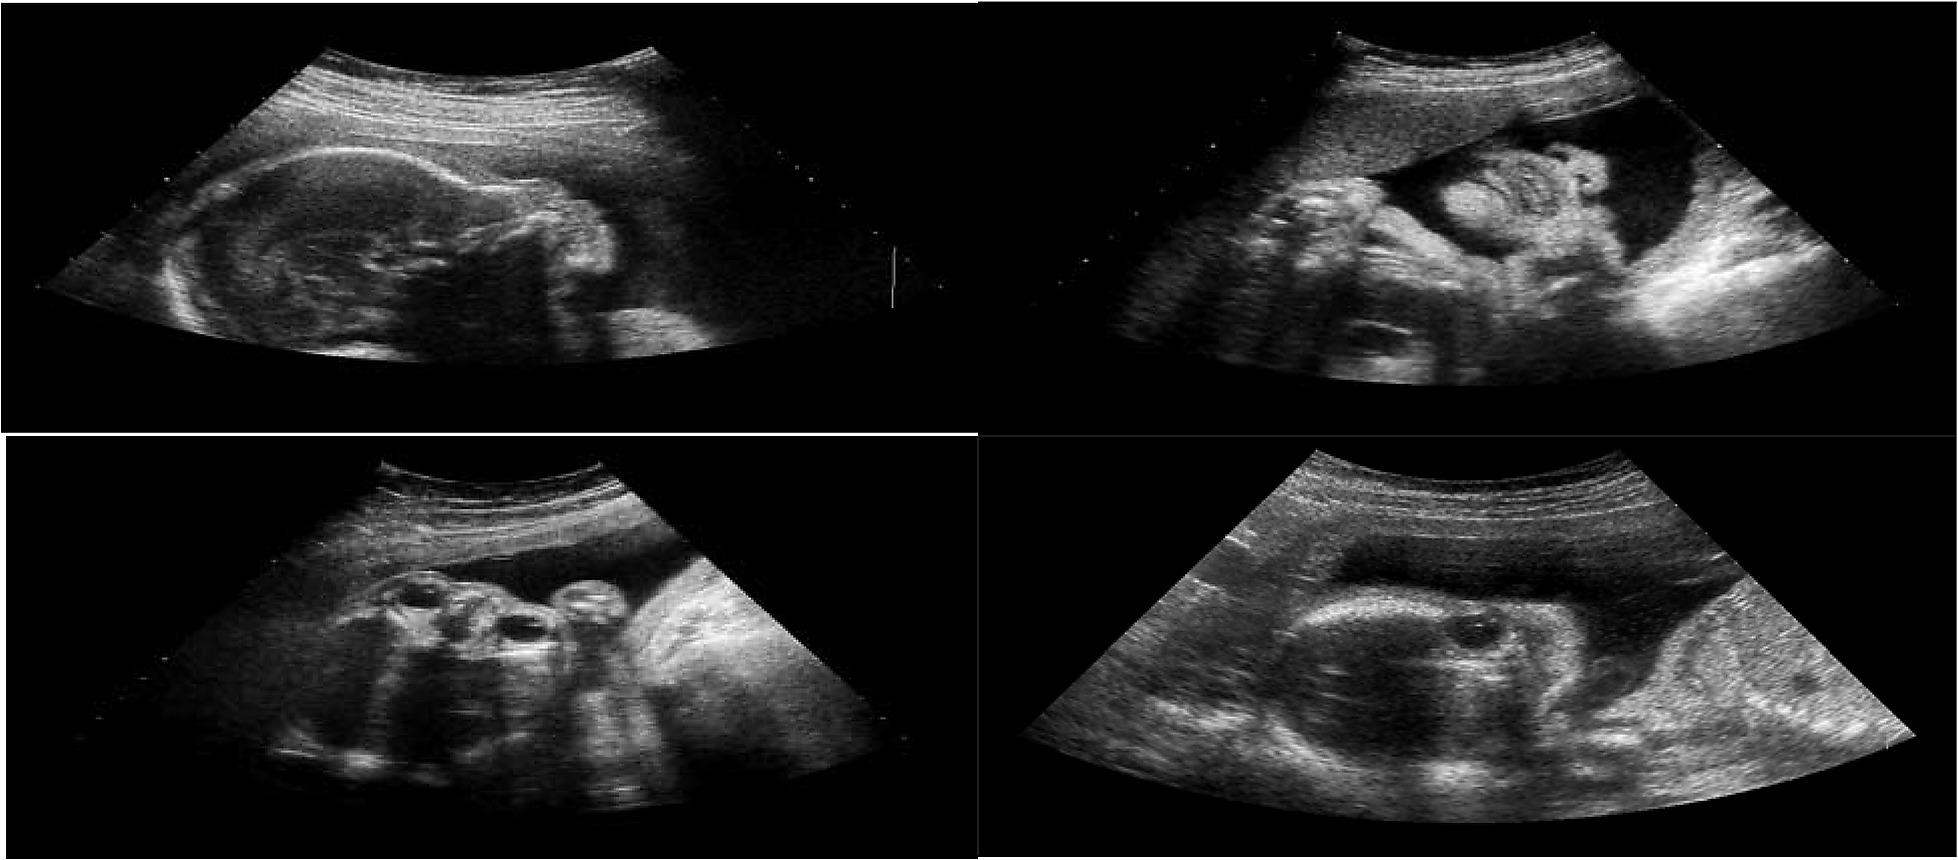

Hình ảnh siêu âm thai

Siêu âm 2D, 3D, 4D

Siêu âm sử dụng sóng âm, không xâm lấn nên rất an toàn, cung cấp hình ảnh 2 chiều, 3 chiều và 4 chiều của thai nhi. Loại siêu âm này đôi khi được sử dụng để giúp bác sĩ phát hiện các bất thường trên khuôn mặt hoặc khuyết tật ống thần kinh.